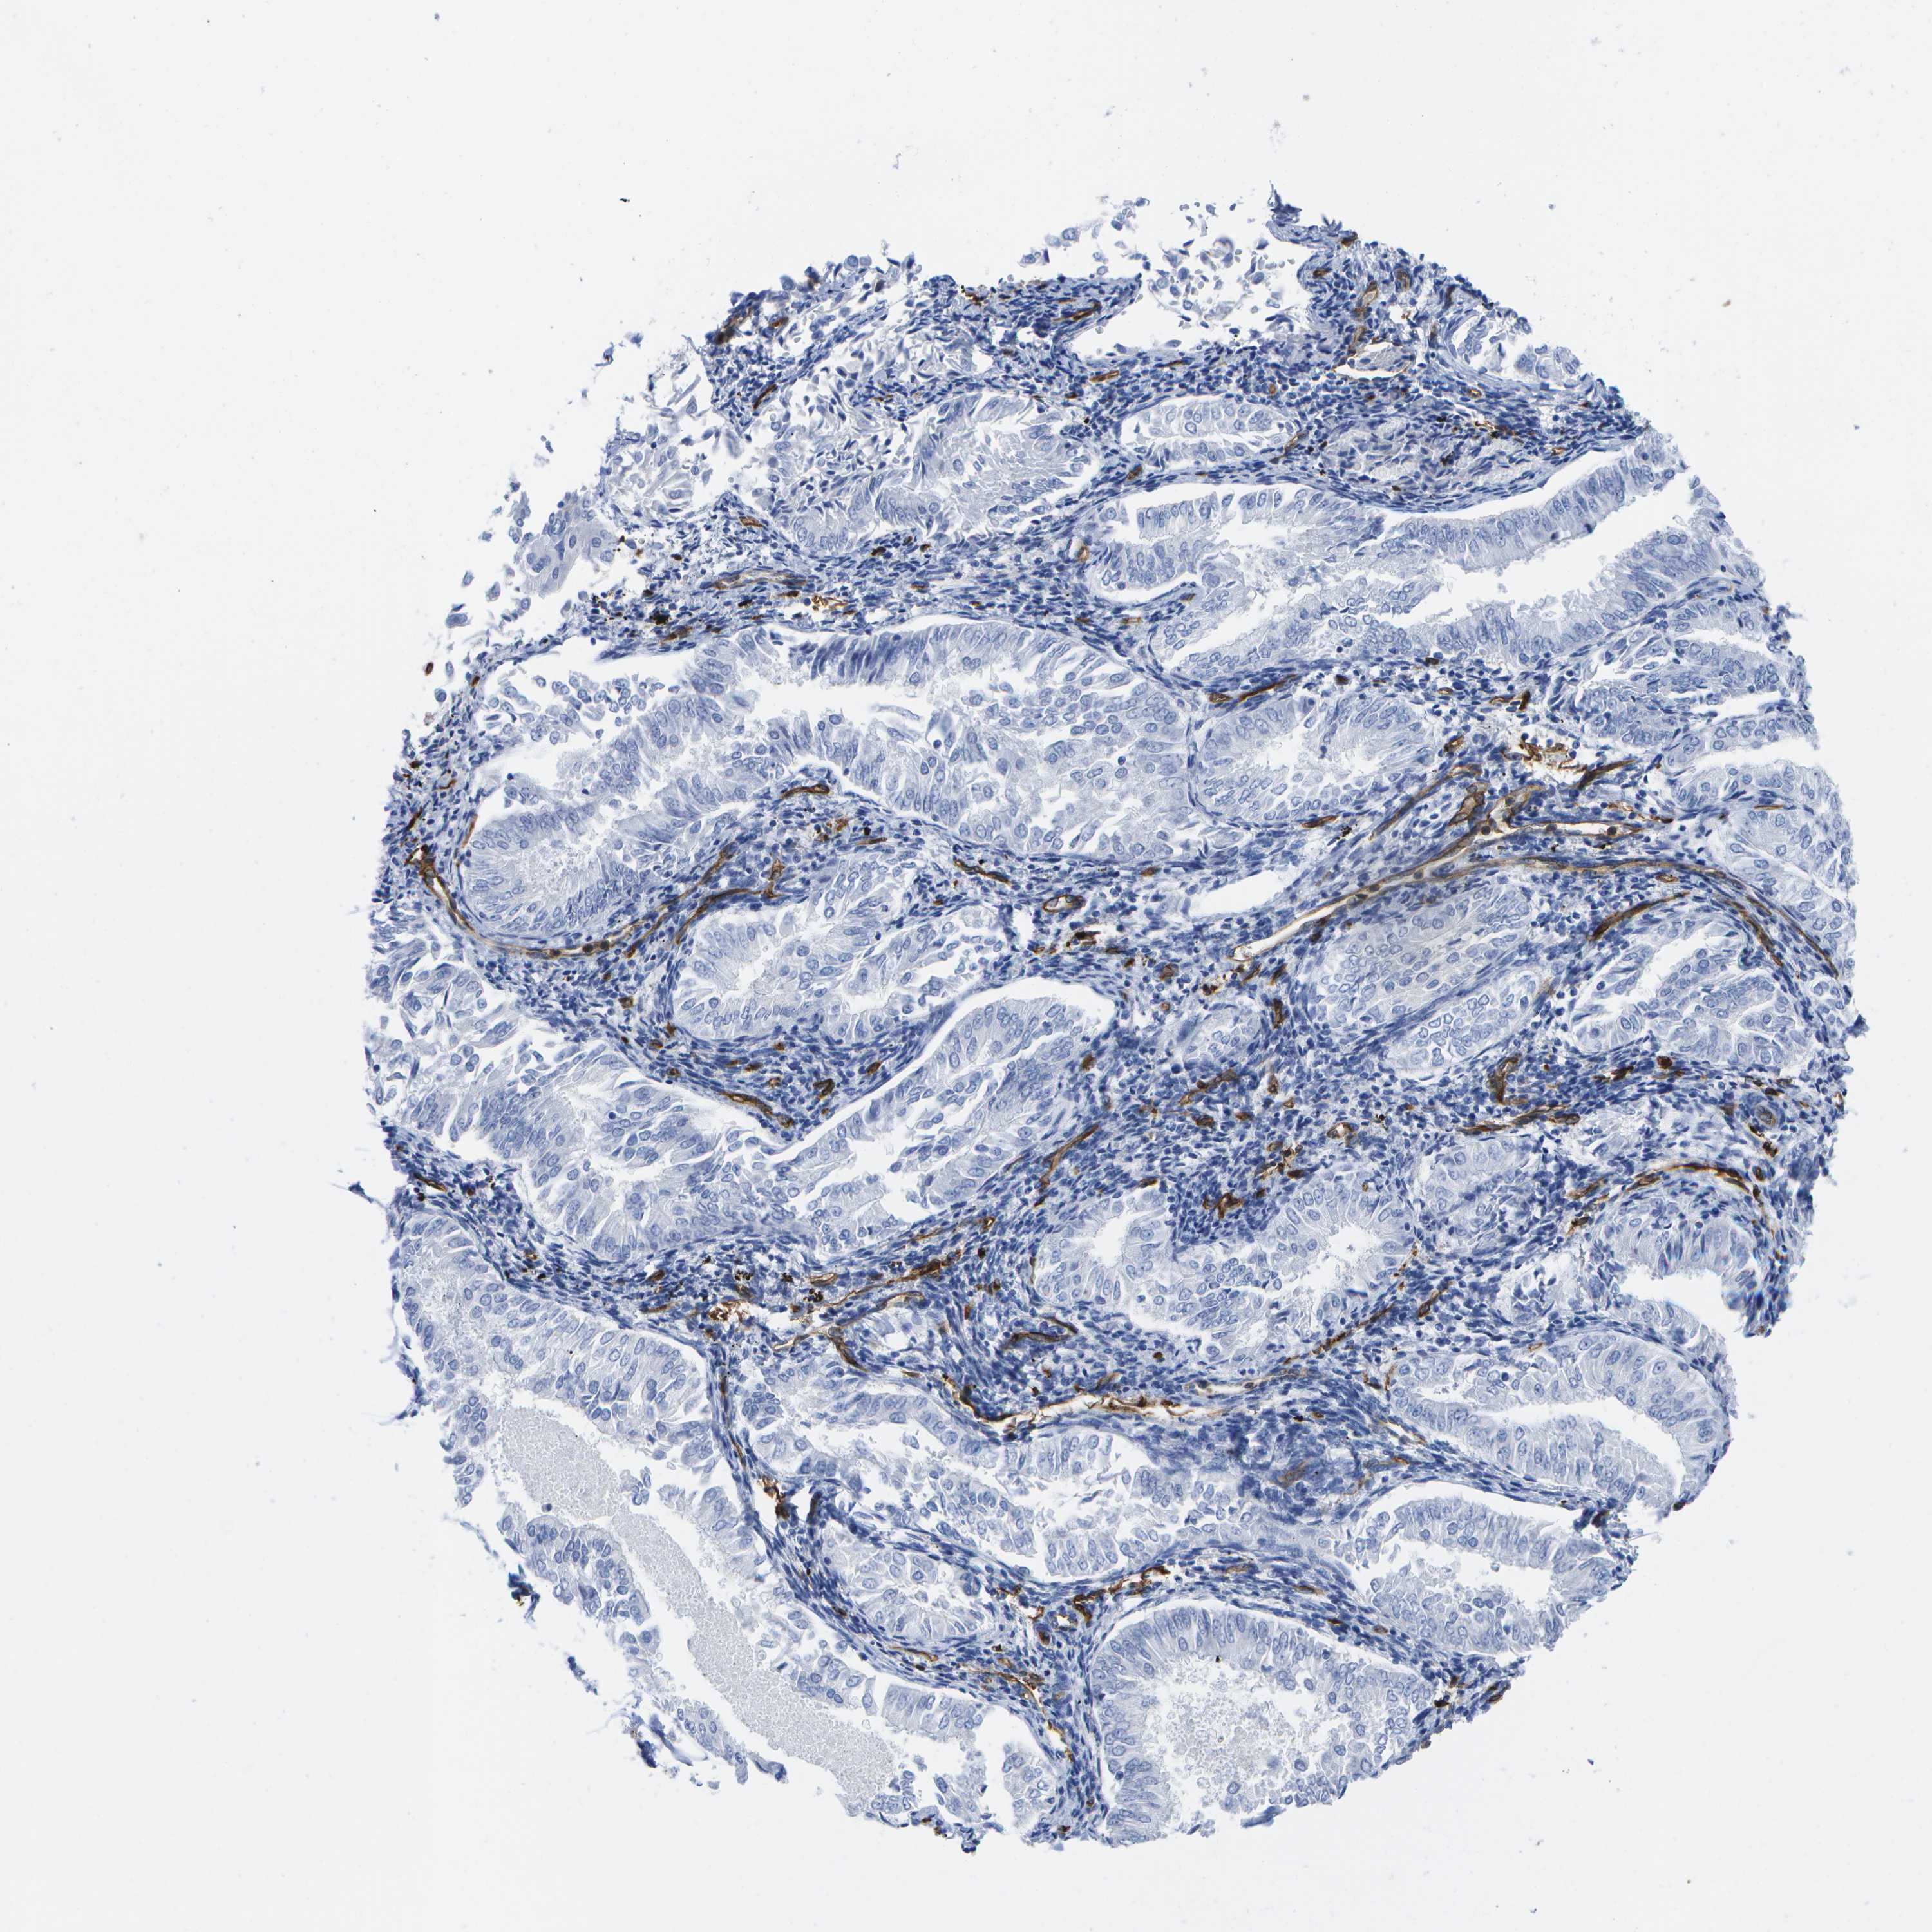

ENDOMETRIAL CANCER - Protein expressioni

A mouse-over function shows sample information and annotation data. Click on an image to view it in a full screen mode. Samples can be filtered based on level of antibody staining by selecting one or several of the following categories: high, medium, low and not detected. The assay and annotation is described here.

Note that samples used for immunohistochemistry by the Human Protein Atlas do not correspond to samples in the TCGA dataset.

Antibody stainingi

Antibody staining in the annotated cell types in the current human tissue is reported as not detected, low, medium, or high, based on conventional immunohistochemistry profiling in selected tissues. This score is based on the combination of the staining intensity and fraction of stained cells.

Each image is clickable and will lead to virtual microscopy that enables deeper exploration of all samples and also displays staining intensity scores, fraction scores and subcellular localization as well as patient and tissue information for each sample.

Antibody HPA017071

Antibody HPA021945

Antibody CAB002510

Staining

High

Medium

Low

Not detected

Intensity

Strong

Moderate

Weak

Negative

Quantity

>75%

75%-25%

<25%

None

Location

Nuclear

Cytoplasmic/membranous

Cytoplasmic/membranous,nuclear